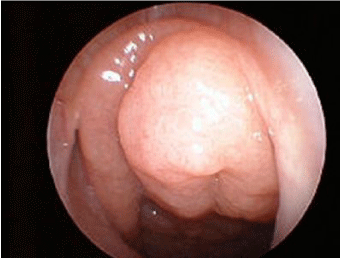

A 45 year old male presented to the ENT OPD, Lok Nayak Hospital, with complaints of nasal obstruction, snoring and repeated awakening at night due to apnea spells. On detailed history, it was found that patient was a chronic smoker for past 25 years. On examination, nasal endoscopy revealed a pale lobulated mass in the nasopharynx (Figure 1). Contrast enhanced CT scan showed a non-enhancing mass in the nasopharynx, extending upto bilateral nasal cavity, suggestive of adenoid hypertrophy (Figure 2). Nasal endoscopic biopsy was done which was suggestive of lymphoid hyperplasia. The patient was managed conservatively for 3 months with steroid nasal spray. However, there was no improvement in the symptoms and patient was planned for surgery. Transnasal endoscopic powered adenoidectomy was done under general anesthesia. Post-operative biopsy report was suggestive of adenoid hyperplasia. Adenoidectomy resulted in resolution of symptoms and immediate improvement in sleep. Topical steroid nasal spray was continued for one year postoperatively. After one year follow up, the patient was asymptomatic. There was no residual tissue in the nasopharynx or any recurrence.

Figure 1: